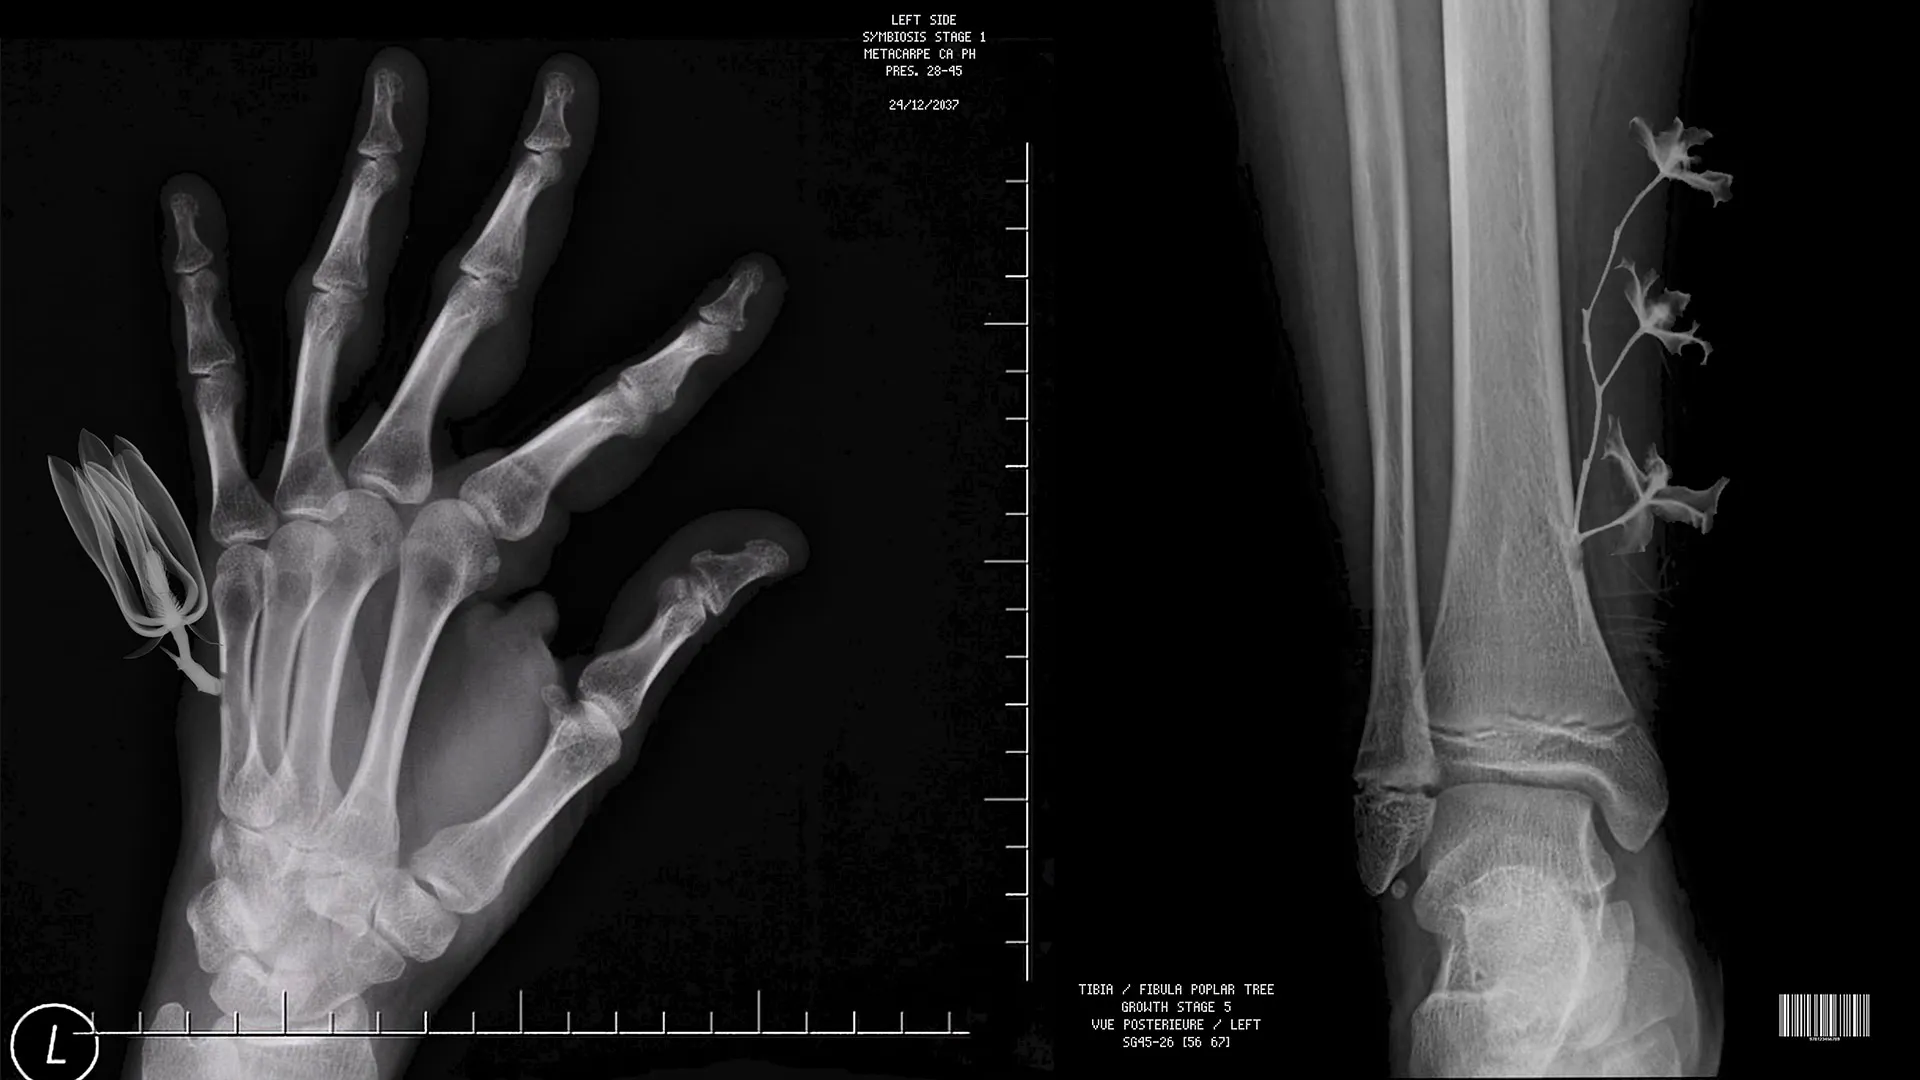

Using bones and wood as a case study for this possible blend, Botanical Bodies looks at the implications of human symbiosis with the vegetal kingdom. Through extracting a wooden bone from a living tree and implantating it into the human body, this work imagines how the distinctions between humans and plants, crowds and forests, bone and wood may fade away towards a new synergy.

The similarities in structure between human organs and plants has become a focus for scientists around the world. For example, one study has combined cardiac tissue and spinach (using decellularized plants as perfusable tissue engineering scaffolds, 2017, Gershlak-Hernandez-Fontana, Worcester Polytechnic Institute), and another has explored using rattan wood for bone growth (From Wood to bone: multi-step process to convert wood hierarchical structures into scaffolds for bone tissue engineering, 2009, Tempieri-Srio-Ruffini-Celloti-Lesci-Roveri).

We are all intimately familiar with our bones in terms of their shape, the movements they allow, the structure they create, however, we don’t visually see them as a material in the way we interact with our skin, for example. Given that they remain unseen, wooden bones have similarities to human bones in terms of their texture, warmth and weight. Although metal is traditionally used to repair bones, it always acts as a support rather than seamlessly blending into the body. Wood as an organic matter seems more likely to be accepted by the body as it can merge with existing tissues.

However, it is interesting to consider how the perceived autonomy of the human body can be easily challenged. For example, there are more foreign cells in the human body (microbes) than human cells, yet I still call myself a human. Moreover, wood and bones share very similar structures on a microscopic level (in terms of mechanical strength, size and structure), making the engineering of wooden bones far from being pure speculation.